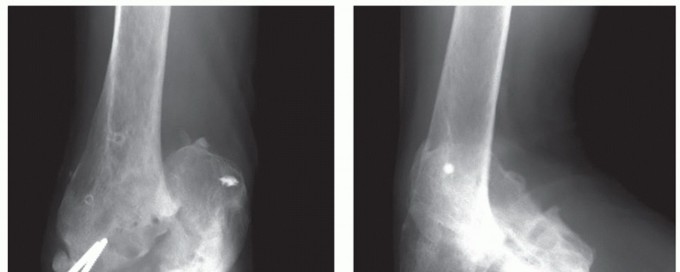

DEFINITION AND PATHOGENESIS Posttraumatic conditions of the elbow represent a spectrum of disorders involving…